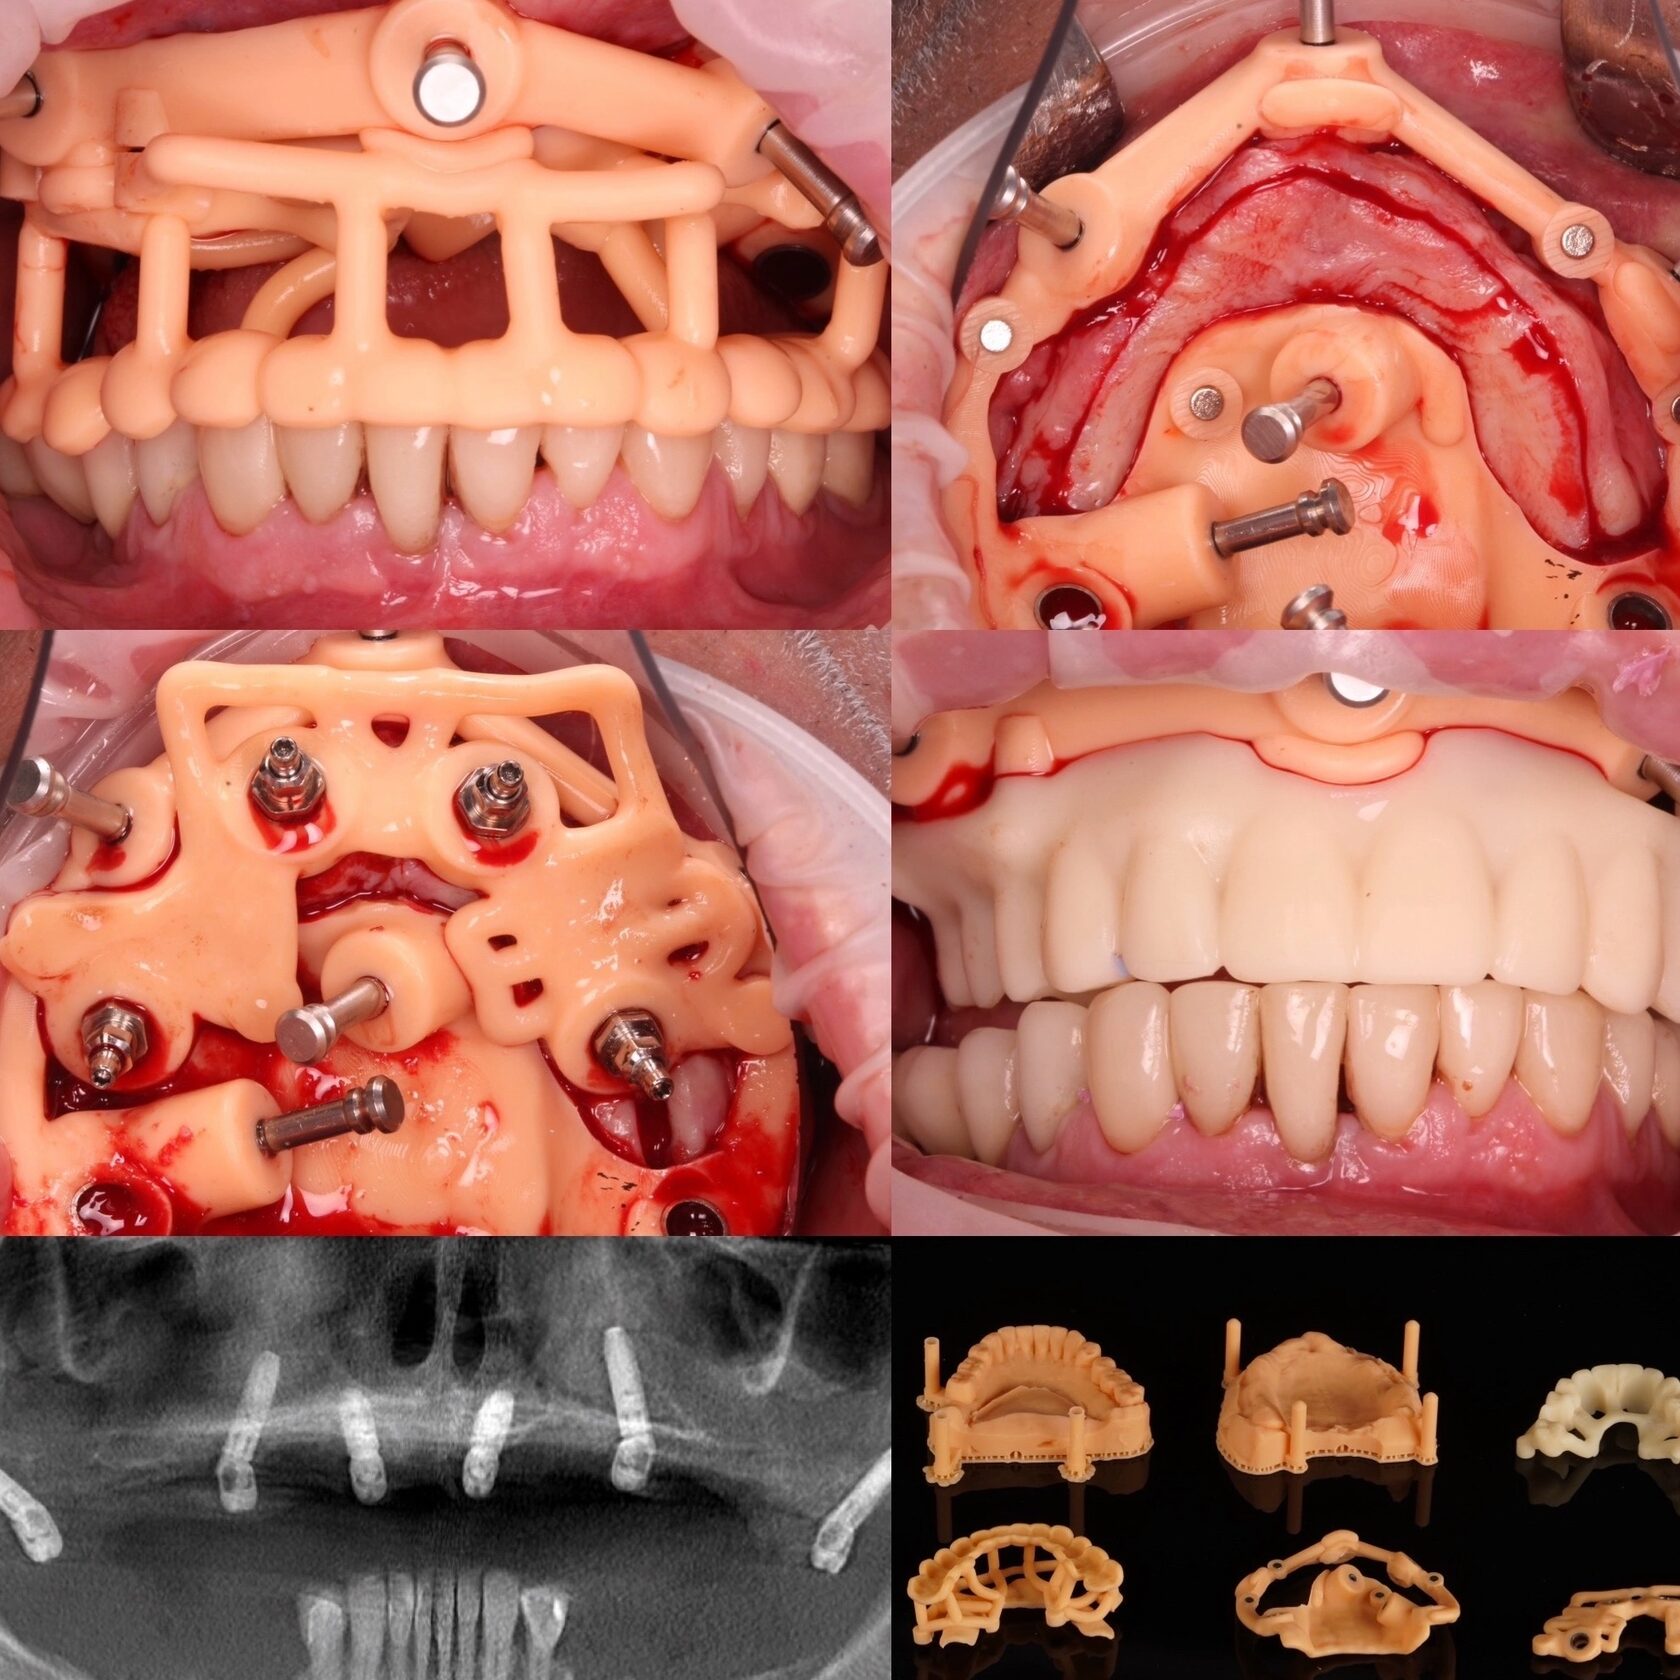

10. Возможность изготовления префабрикованных конструкций. - Готовые одиночные конструкции - Конструкции под вклейку/перебазировку - Сварка опорной титановой балки - Прототипы тотальных работ

Учебный проект 2 – последовательные шаблоны ALL-on-4 на НЧ при умеренной атрофии

Учебный проект 3 – моделирование разборного хир. Шаблона FP1

Моделирование прототипа

Учебный проект 4 – моделирование разборного хир. Шаблона FP3